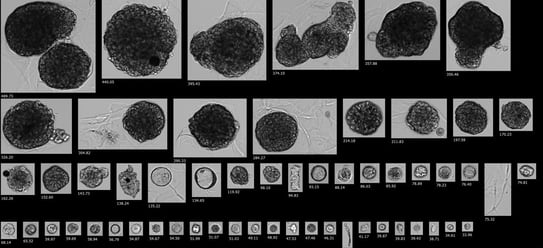

Pictured here: Low-passage tumoroids imaged with brightfield microscopy (top) and with FlowCam, an FIM instrument (bottom). 3D cell clusters cultured in Matrigel® were collected and released from the scaffold matrix before imaging at 4X magnification. The observation of large 3D cell clusters and cluster aggregates with some association of extracellular matrix components is consistent between brightfield microscopy and FIM with FlowCam.

Many 3D cell culture systems, however, are not grown in suspension but are instead grown using scaffold-based systems that can make it difficult to visualize microscopic changes in 3D cell cluster behavior. While there are risks involved with removing the supporting 3D microenvironment for image analysis, monitoring morphological properties is important to ensure culture treatment conditions are appropriate for preserving clinically relevant phenotypes. Recent proof-of-concept work showed FlowCam is effective at characterizing and monitoring low-passage tumoroid models upon release from extracellular scaffolding. Measurements of morphology and cellular behavior tracked in real-time with FlowCam were consistent with data derived from manual brightfield microscopy images, demonstrating FIM as a high-throughput, non-destructive solution for quantitative characterization of precious and complex three-dimensional structures. As an image-based system, FIM provides high-resolution images, particle size distributions, and comparative analysis of 3D aggregate morphologies in real-time. FIM with FlowCam enables rapid processing time and overcomes the labor-intensive challenges of manual microscopy.